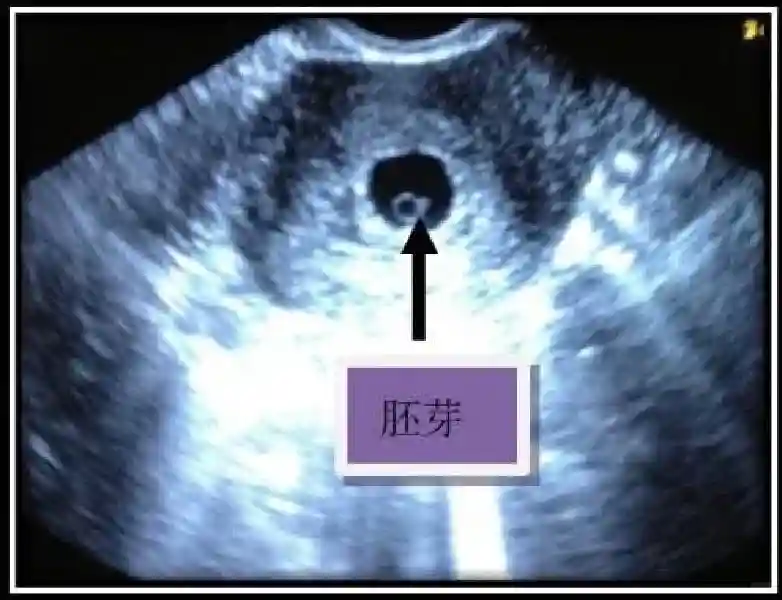

3??胚胎:胚胎通常在6-7周時(shí)可以為超聲顯示,起初為胎芽,表現(xiàn)為卵黃囊一側(cè)局部組織增厚,達(dá)到1 -2 mm 時(shí)才有可能為超聲測(cè)量出來(lái)。達(dá)4-5mm時(shí)可見(jiàn)胎心搏動(dòng),相應(yīng)孕周為6-6.5周,妊娠囊大小為13-18mm。胚芽長(zhǎng)度≥7㎜時(shí)仍未見(jiàn)心管搏動(dòng),提示胚胎停止發(fā)育。胚胎的出現(xiàn)和妊娠囊直徑的關(guān)系:妊娠囊直徑> 16 mm 時(shí),經(jīng)陰道超聲應(yīng)顯示胚胎。妊娠囊直徑> 25 mm 時(shí),經(jīng)腹超聲均應(yīng)顯示胚胎。